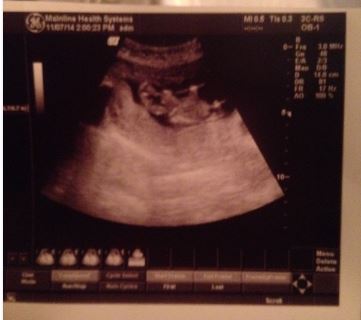

Here's my scan which I think is kind of grainy....any guesses?

I don't think baby is in the right position, although it's rather hard to tell. Even zoomed in, I don't see anything I'd feel comfortable guessing on. Sorry!

Very unclear but maybe boy? Wouldn't bet on it though.

Thanks guys for replying to my post! I have another scan scheduled a few days before Christmas so hopefully I'll find out for sure then. I am definitely hoping for a boy though